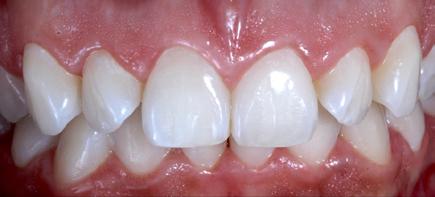

Reshaping of teeth and diastema closure with G-aenial A’CHORD. Courtesy of: Dr Andres Silva, Spain